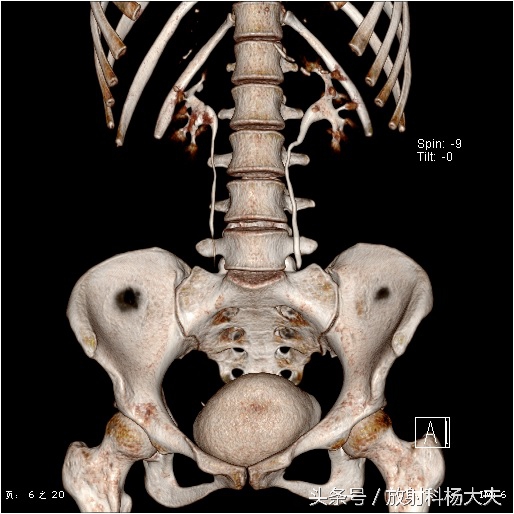

女孩的肾功能是好的,能够看到VR图像里双肾盂和输尿管显影很清楚。